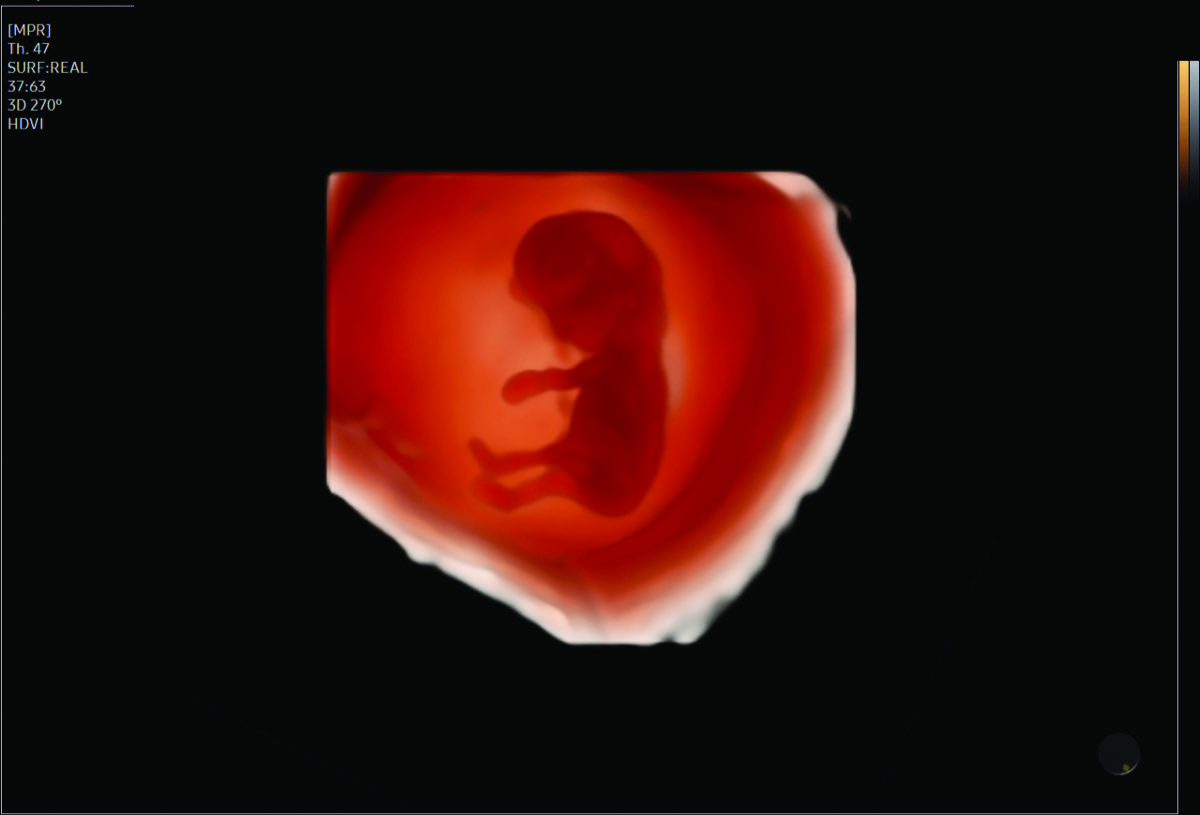

Comprehensive, advanced and expert MFM care for high-risk pregnancies

- Fetal anomalies